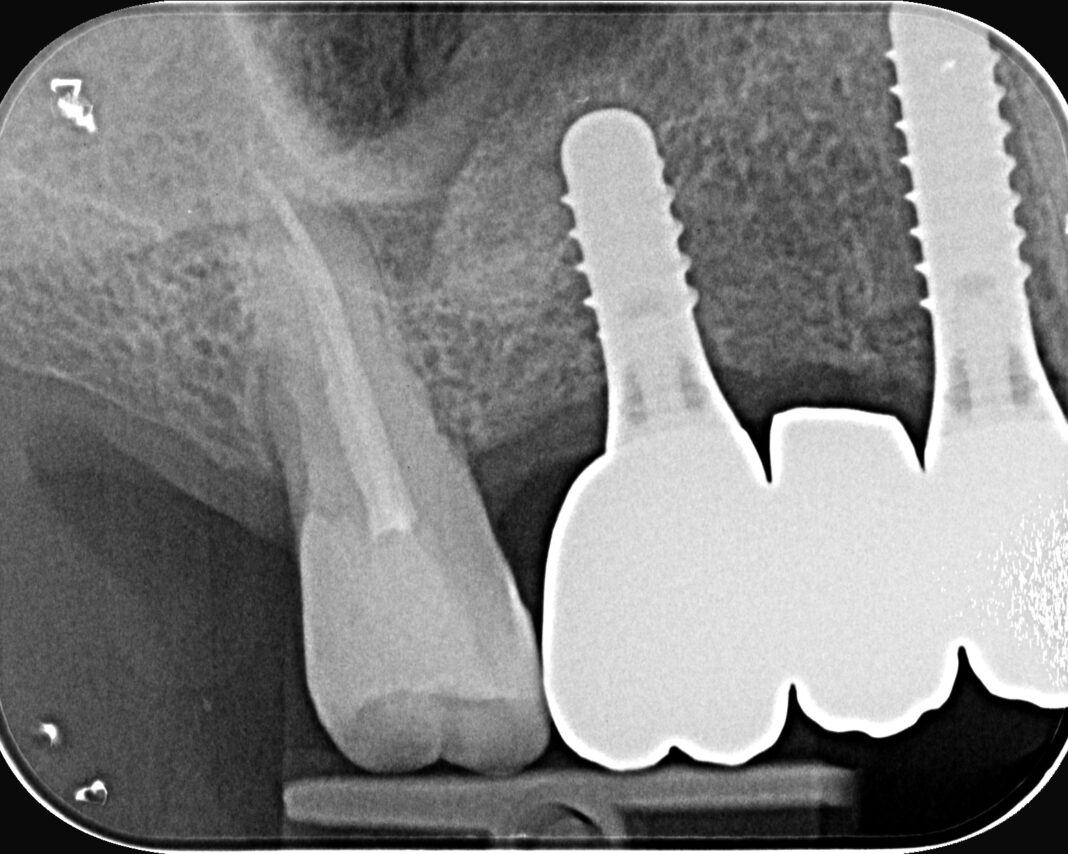

Si descrive una riabilitazione …